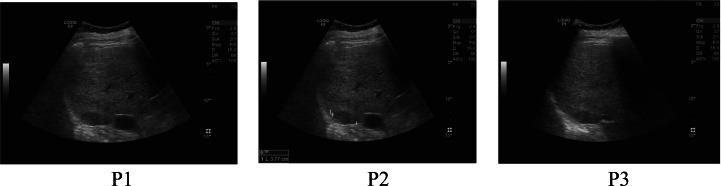

In this proposed work, a dual image watermarking algorithm is used to protect the data against copyright violations. In this work, the DICOM image is used as a host image. Two watermark images used are the MNNIT logo and the personal data of the patient. This method utilizes the advantages of Schur decomposition, lifting wavelet transform (LWT), discrete cosine transform (DCT) and singular value decomposition (SVD). The scaling factor is a vital parameter of watermarking technique. The firefly optimization technique is used to get the optimized scaling factor. The Speeded-up robust features (SURF) are used for watermarking authentication. To evaluate the performance of the proposed algorithm, peak signal-to-noise ratio (PSNR), normalized correlation coefficient (NCC), and structural similarity index measurement (SSIM) are used. The proposed method is tested against various attacks such as Salt and Pepper noise, Gaussian noise, Gaussian low pass filter, Average filter, Median filter, Histogram equalization, Sharpening, Rotation and Region of interest filtering. The proposed algorithm shows a high level of robustness and imperceptibility. It is found that the features of the input host image and the watermarked image are matching correctly on applying the SURF technique.

在这项拟议的工作中,采用了一种双图像水印算法来保护数据不被侵犯版权。在这项工作中,DICOM图像被用作宿主图像。所使用的两个水印图像分别是MNNIT标志和患者的个人数据。该方法利用了舒尔分解、提升小波变换(LWT)、离散余弦变换(DCT)和奇异值分解(SVD)的优点。缩放因子是水印技术的一个关键参数。采用萤火虫优化技术来获得优化后的缩放因子。加速鲁棒特征(SURF)用于水印认证。为了评估所提算法的性能,使用了峰值信噪比(PSNR)、归一化相关系数(NCC)和结构相似性指数测量(SSIM)。所提方法针对各种攻击进行了测试,如椒盐噪声、高斯噪声、高斯低通滤波器、均值滤波器、中值滤波器、直方图均衡化、锐化、旋转和感兴趣区域滤波。所提算法显示出高度的鲁棒性和不可感知性。发现在应用SURF技术时,输入宿主图像和水印图像特征匹配正确。